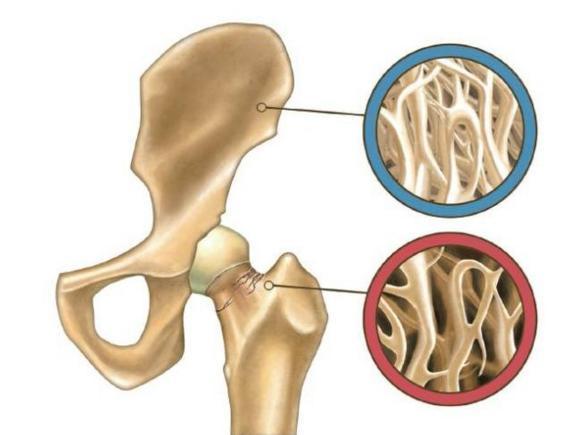

5.骨傷康復:各種骨關節炎,肌肉拉傷、挫傷,髖膝關節置換等骨科術后運動功能恢復。

骨質疏松治療儀